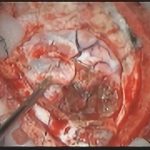

術中写真

摘出 前

摘出 中